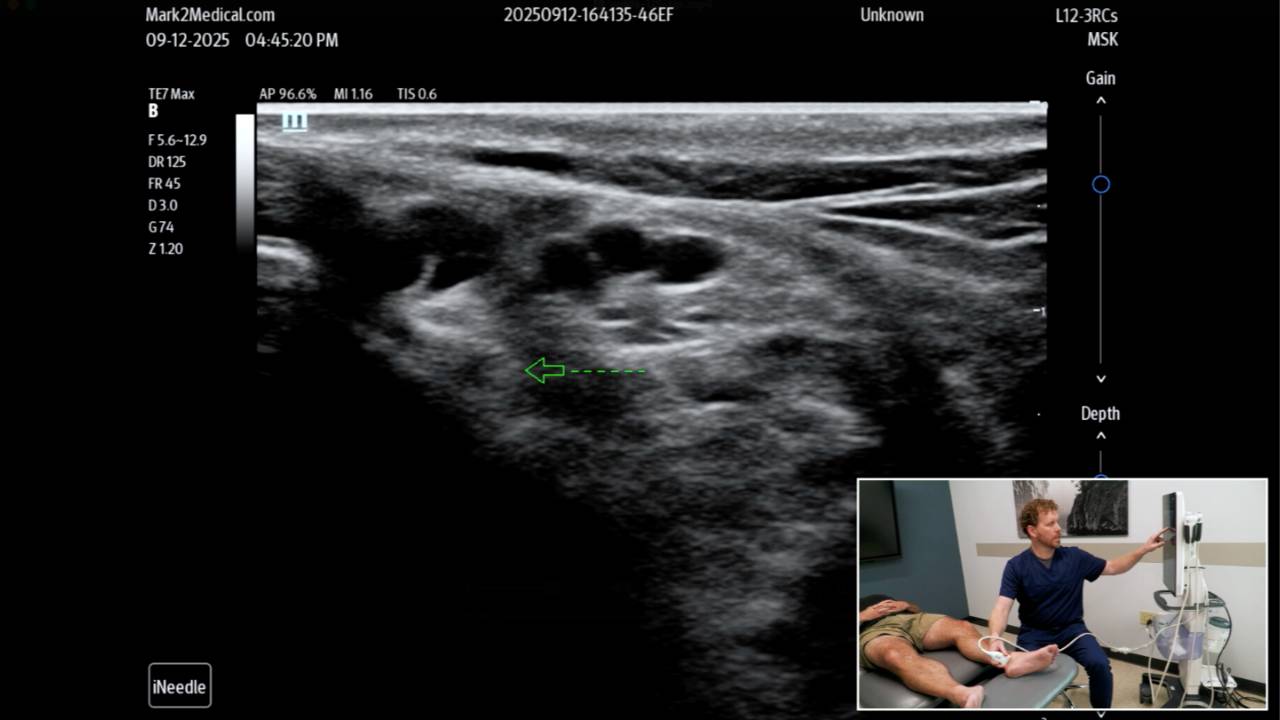

Lower Extremity Nerve Blocks and Scanning

Eric Phillippi, MD & David C. Wang, DO lead this advanced, hands-on intensive focused on comprehensive ultrasound-guided nerve scanning and hydrodissection for lower-extremity pain patterns. You’ll learn a practical, repeatable approach to identifying and treating key nerve entrapments and irritation points—from the pelvic plexus through the tibial, peroneal, sural, and plantar nerves—with an emphasis on sonoanatomy, probe positioning, needle visualization, and safe technique. The session includes live model scanning and real-world clinical pearls to help you apply these interventions immediately in practice. Sunday, March 1 | 8:00 AM–12:00 PM